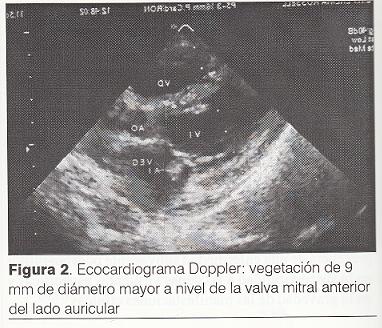

Radiografía de tórax: cardiomegalia y edema pulmonar (figura 1).